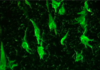

What are pick bodies?

Histological/pathological finding of Alzheimer’s disease

- pick bodies = spherical aggregates of Tau proteins in neurons

- visible via silver stain